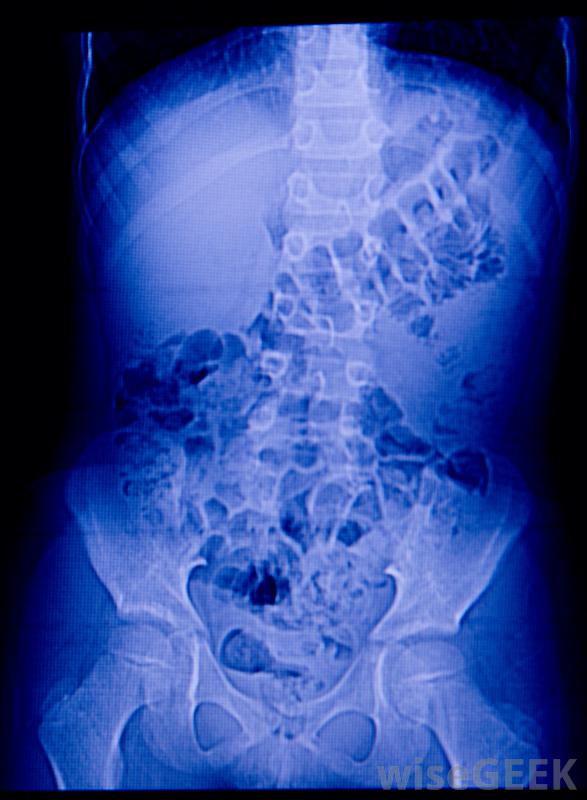

腹部X光片有助于脓肿的诊断在大多数情况下,腹部脓肿是由其他疾病引起的,如阑尾破裂或寄生虫感染。这些情况可能会造成腹部的脆弱区域,细菌很容易侵入。与皮肤上的外部脓肿不同,腹部脓肿可能不是明显到足以引起症状。常见症状包括腹泻、恶心、腹痛、发冷,腹部脓肿可引起腹痛腹部脓肿的主要治疗方法包括使用抗生素和引流脓液及其他内容物的导管,一般是通过皮肤插入脓肿内,留在原位直到没有感染的迹象。在非常严重的情况下,病人可能需要手术从源头清除脓肿

在非常严重的情况下,腹部脓肿可能破裂并开始将感染引流至腹腔。诊断腹部脓肿可能需要使用超声波、X光片,或者是电脑断层扫描。更罕见的是,可能需要小手术来诊断脓肿。在大多数病人中,无需手术切除即可成功治疗。